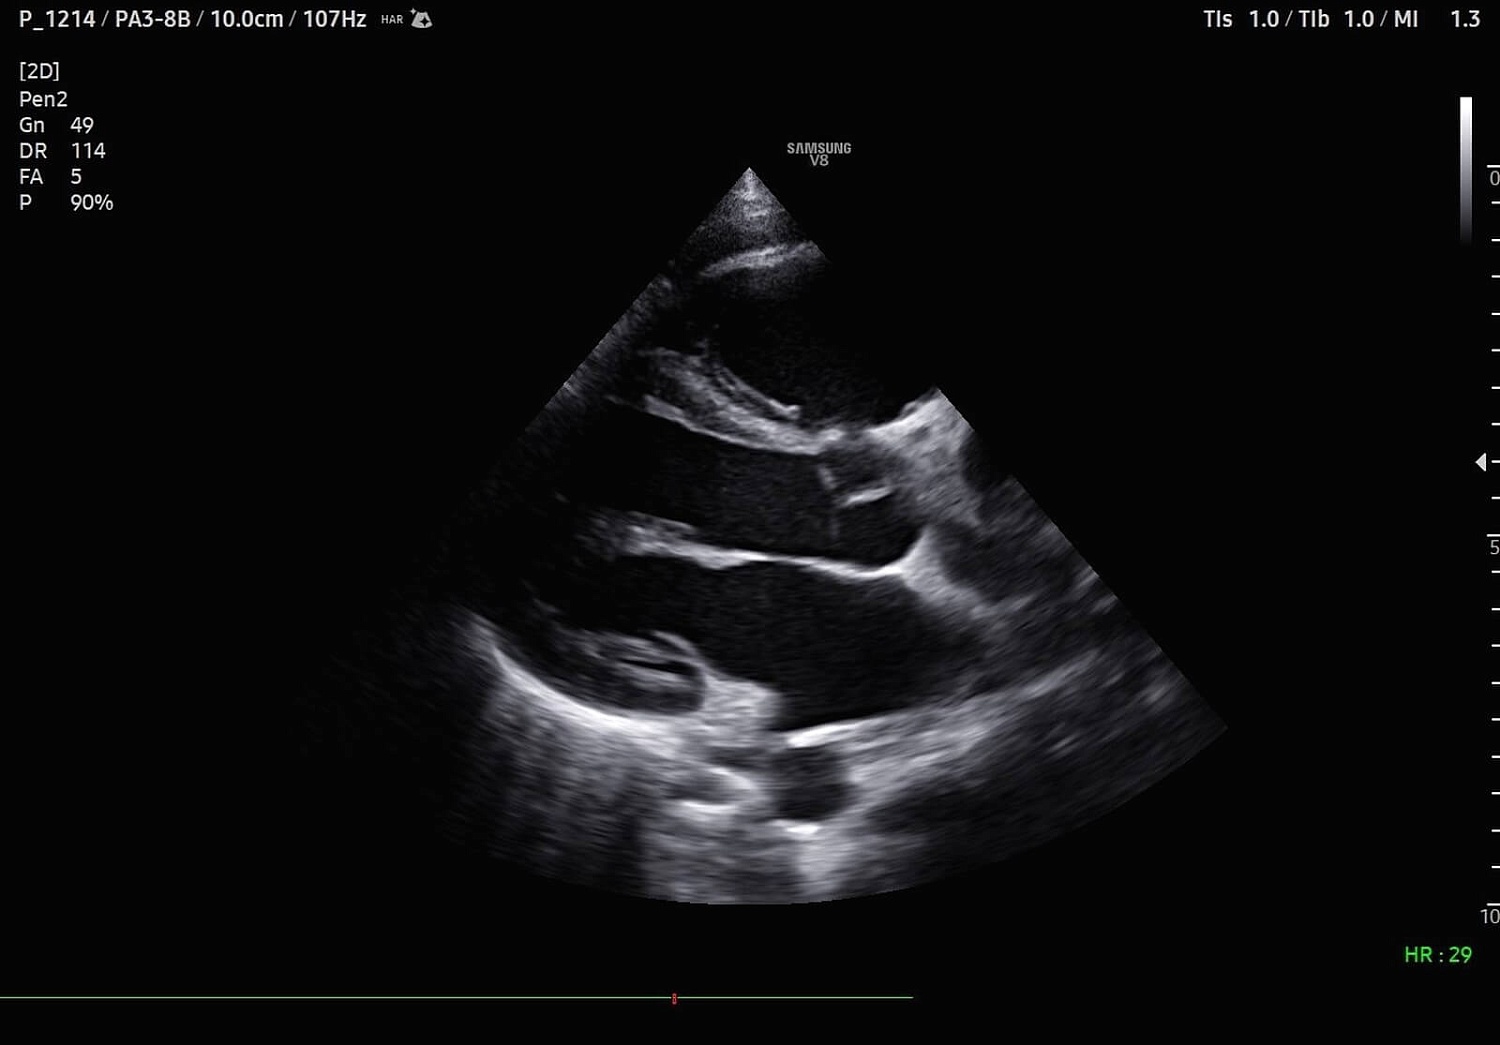

Рады сообщить, что в ассортименте нашей компании появился ультраинновационная УЗИ система экспертного (премиального) класса Samsung Medison V8. Этот ультразвуковой аппарат, функционирующий на базе искусственного интеллекта, предназначен для проведения исследований любого уровня сложности в области онкологии, пренатальной диагностики, неонатологии, гинекологии, урологии, а также общей радиологии, ортопедии, кардиологии и ангиологии.

УЗИ аппарат V8 отличается превосходным технологическим оснащением, высочайшим уровнем визуализации и удобством использования. Многочисленные решения позволяют оптимизировать рутинный диагностический процесс, автоматически осуществляя измерения, расчеты и классифицируя выявленные изменения. Это значительно сокращает время на исследование и в разы повышает диагностическую точность. Помимо уже знакомых функций Biometry Assist, AutoIMT, 2D Follicle, 2DNT и пр., в модели реализована опция автоматического сегментирования структур сердца, автоизмерения с технологией Heart Assist, определение положения срединного нерва в поперечном сечении Nerve Track.